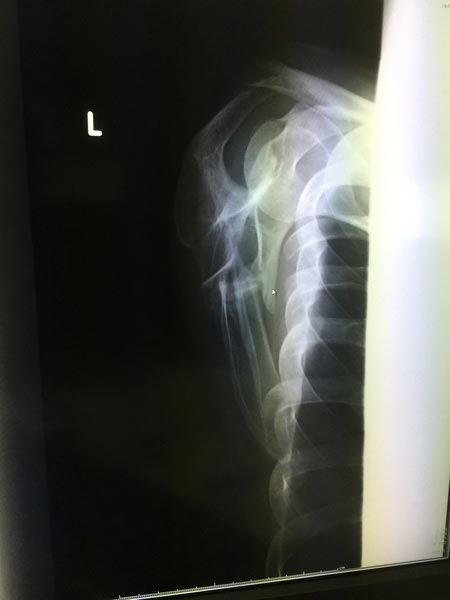

去年バイクで転倒してしまい、肩甲骨と肋骨を折っていました。

肋骨は2月頃に繋がってきましたが、なかなか肩甲骨が・・・

本日の検査で、少し骨が付き始めていました。